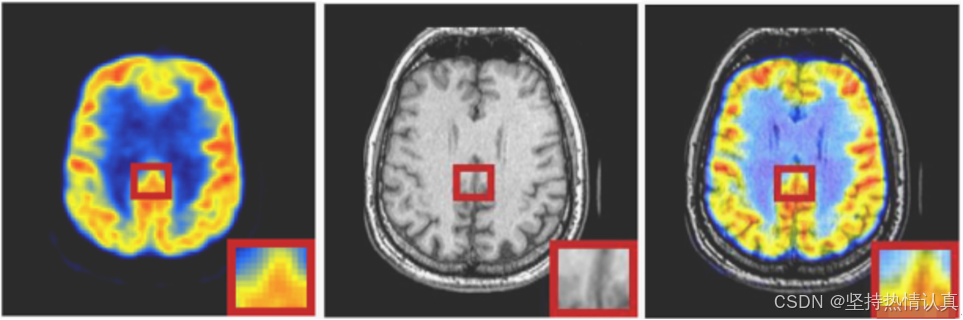

TransFuse: A Unified Transformer-based Image Fusion Framework using Self-supervised Learning

这篇论文提出了一种名为TransFuse的新框架,它是一个统一的基于Transformer的图像融合框架,利用自监督学习来提升图像融合效果。该方法旨在克服传统端到端图像融合方法因缺乏特定任务训练数据和相应的真实标签而容易过拟合的问题,同时避免了两阶段方法由于自然图像和不同融合任务之间的领域差距导致的性能受限。

TransFuse设计了一个新颖的编码器-解码器结构,并提出了一个基于破坏-重建的自监督训练方案,鼓励网络学习特定任务的特征。具体来说,对于多模态图像融合、多曝光图像融合和多焦点图像融合,分别设计了三种基于像素强度非线性变换、亮度变换和噪声变换的破坏-重建自监督辅助任务。为了促进不同融合任务间的相互促进并增加训练网络的泛化能力,这三种自监督辅助任务通过随机选择其中一种来破坏自然图像的方式整合在一起。

此外,TransFuse还设计了一个结合了CNN和Transformer的新编码器,以在特征提取过程中同时利用局部和全局信息。实验结果显示,该方法在多模态图像融合、多曝光图像融合和多焦点图像融合任务中都达到了最新的最优性能,既在主观评价也在客观指标上超越了现有方法。